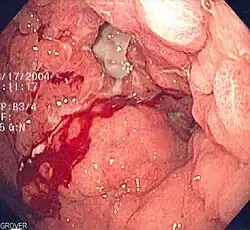

![]() Una úlcera estomacal que fue diagnosticada como cáncer en una biopsia y extirpada quirúrgicamente. | ||